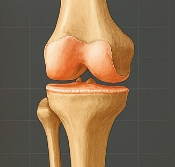

무릎 연골은 대퇴골(허벅지뼈)과 경골(정강이뼈) 사이에 존재하며, 충격을 흡수하고 관절을 부드럽게 움직이게 도와줍니다. 연골이 마모되거나 찢어지면 관절 간 마찰이 심해지고, 염증과 통증이 발생합니다. 대표적인 형태는 다음과 같습니다.

- 반월상연골 손상: 무릎 중앙의 C자 형태 연골이 찢어짐

- 연골연화증: 무릎 연골이 말랑해지며 기능 저하

- 연골 마모: 반복적 충격으로 연골이 닳아 없어짐